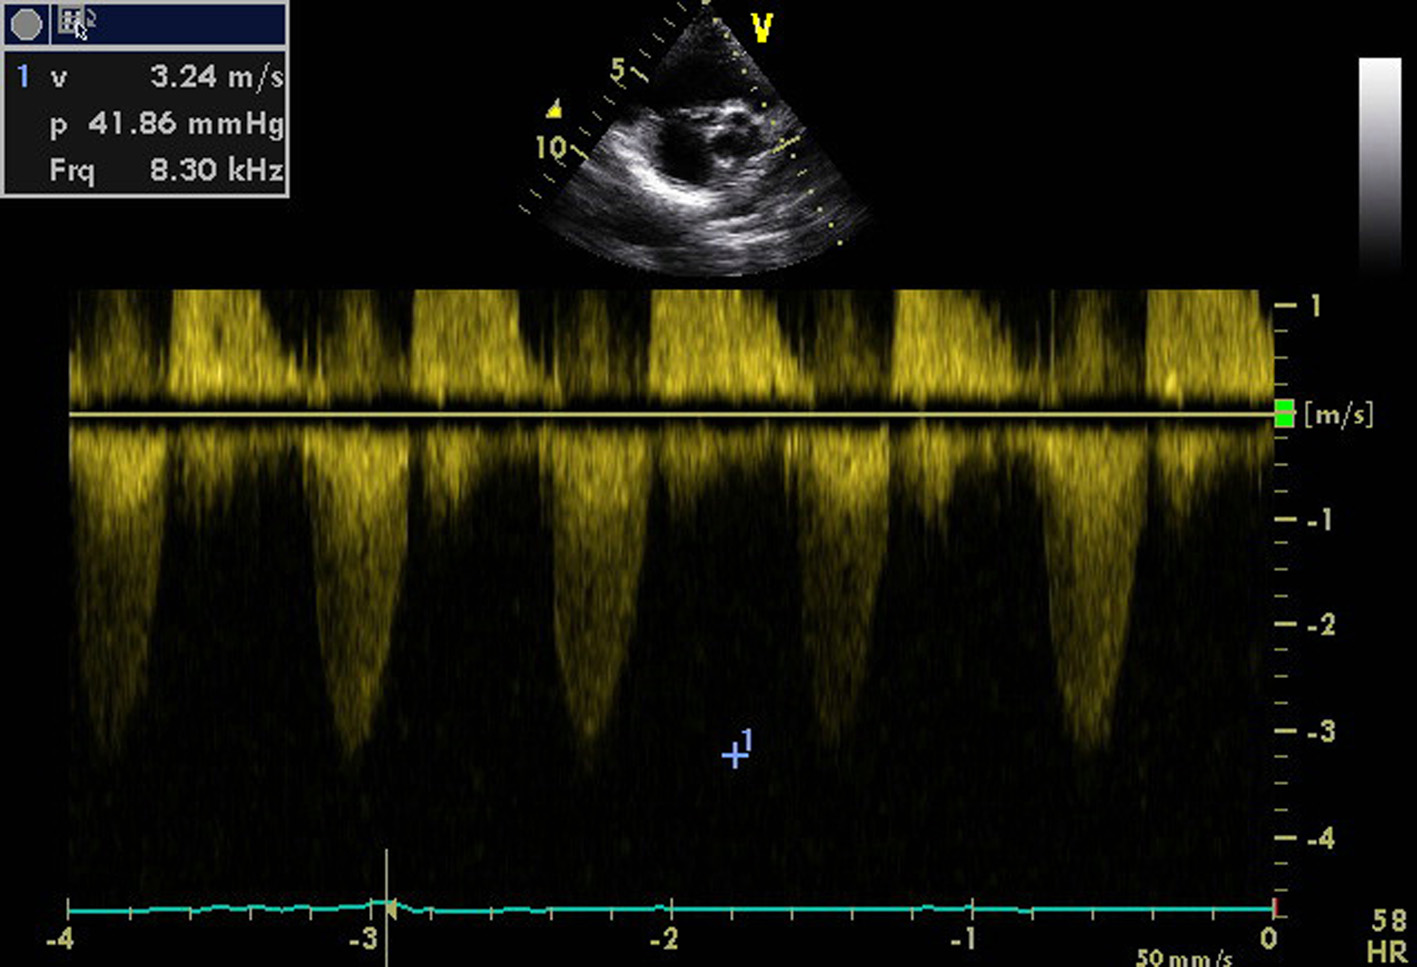

Figure 1. Transthoracic echocardiogram of apical four-chamber view showing thickened and doming mitral valve and tricuspid valve.